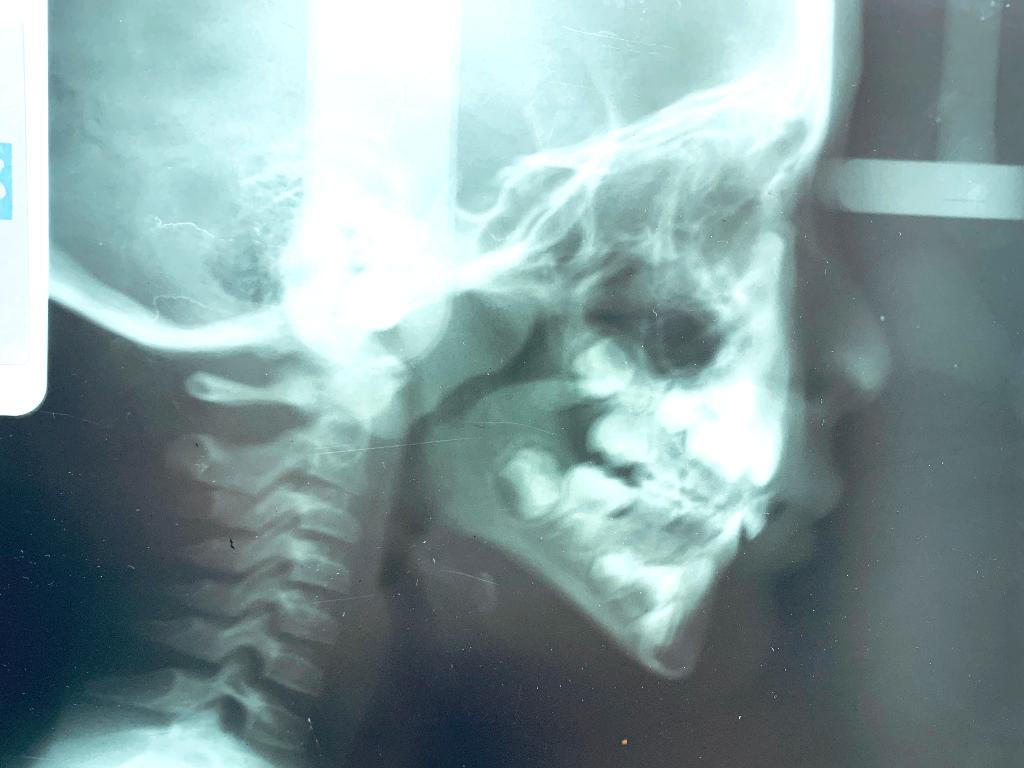

LATERAL

Todo en norma en tamaño esqueletal

Retroposicion de maxilares